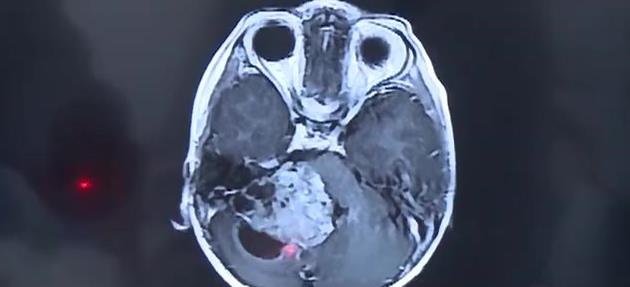

2岁男童走路不稳 竟是患了脑瘤